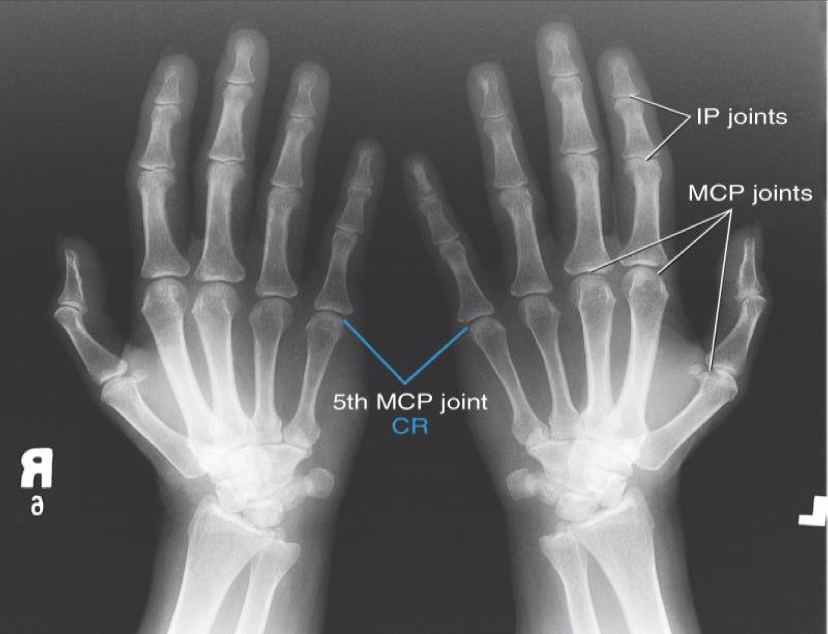

Bilateral AP Oblique hands “ Ball Catchers”

- Special projection for early detection of rheumatoid arthritis and fractures at the base of the 5th metacarpal

- Both hands are imaged together

- This projection is usually substituted for the PA oblique

CR

Centered between hands @ level of MCP’s

Evaluation Criteria for “ Ball Catchers”

• Bilateral hands in 45° oblique position

• Midshafts of second to fifth metacarpals and base of phalanges not overlapped

• Thumb not superimposed over metacarpals

• MCP joints should open